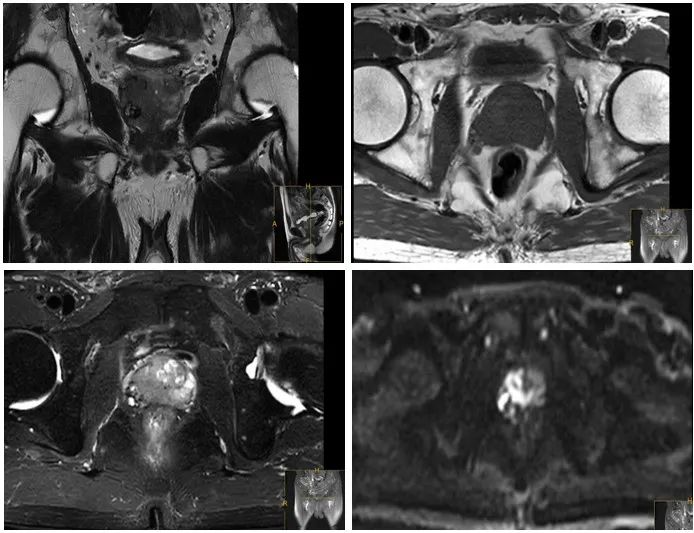

前列腺MRI+DWI:前列腺右侧外周代占位性病变,考虑肿瘤性病变;Th11、L1、3、5椎体及多发附件、骶骨、双侧髂骨、双侧耻骨上支及右侧耻骨下支多发异常信号影,考虑肿瘤性病变。

图1 前列腺MRI+DWI检查结果